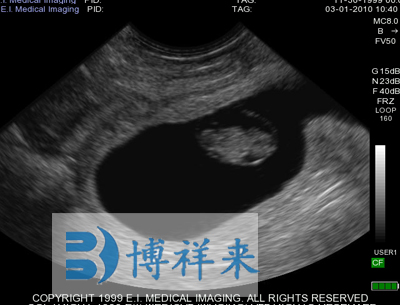

使用对象:牛、马等动物

| 尺寸和重量 | Ibex Lite:IP56 -黄色;8.9”L,7”W,2.2”D;3.61磅(1.63Kg) | 应用范围 | 牛,马,宠物,猪,珍惜动物和小反刍动物等 |

| 超声类型 | 数字超声 | 产科软件 | 各种动物妊娠期参数表格 |